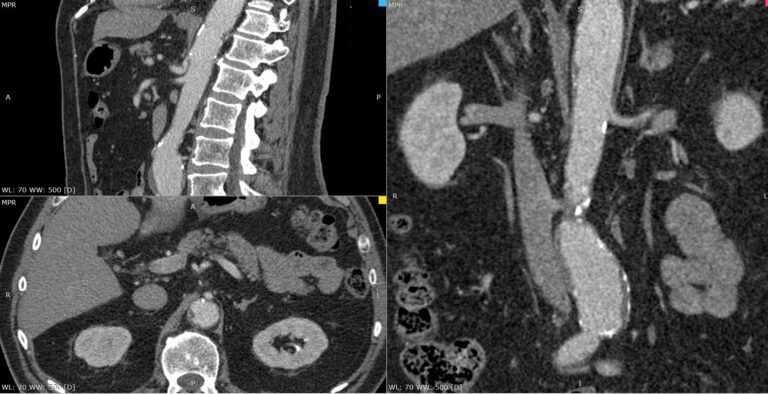

При возникновении подозрения на стеноз чревного ствола за счет экстравазальной компрессии при синдроме Данбара исследование проводится с функциональными пробами, на вдохе и на выдохе для уточнения зависимости степени сужения от фазы дыхания. При выполнении функциональных проб также возможно определить сдавление правой почечной артерии или левой почечной вены.

Мультиспиральная компьютерная томография с внутривенным болюсным контрастированием является быстрым, безопасным и неинвазивным (то есть не требующий вмешательства в организм пациента) способом диагностики патологии чревного ствола. Метод основан на использовании ионизирующего излучения и способности тканей поглощать рентгеновские лучи.

В диагностических центрах «Доступная медицина» КТ чревного ствола выполняется на современных мультиспиральных компьютерных томографах экспертного класса TOSHIBA AQUILION. Аппараты послойно сканируют исследуемую область с шагом от 0,5 мм, при этом для улучшения визуализации сосудистого русла в вену пациента вводится йодсодержащий контрастный препарат.

Контраст хорошо поглощает рентгеновские лучи, что обеспечивает высокую контрастность изображений брюшной аорты и висцеральных ветвей на снимках. С помощью инновационных цифровых приложений данные, полученные при сканировании, реконструируются в трехмерные изображения сосудистой системы. Методика обеспечивает точную и достоверную диагностику стенозов чревного ствола, при этом современные технологии, применяемые при сканировании, сводят к минимуму лучевую нагрузку на пациента.

На снимках мультиспиральной компьютерной томографии с контрастированием хорошо визуализируется брюшная часть аорты, чревный ствол, брыжеечные артерии. При этом можно выявить признаки поражения висцеральных ветвей аорты, то есть сужение просвета сосудов за счет: